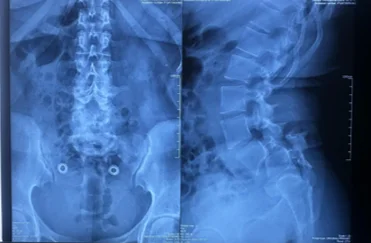

Before & After Clinical Gallery

We showcase real patient cases (with consent), including:

• Pre- and Post-operative MRIs and X-rays

• Disc Herniations, Stenosis, and Spondylolisthesis cases

• Visible improvement in alignment and decompression

Before

After